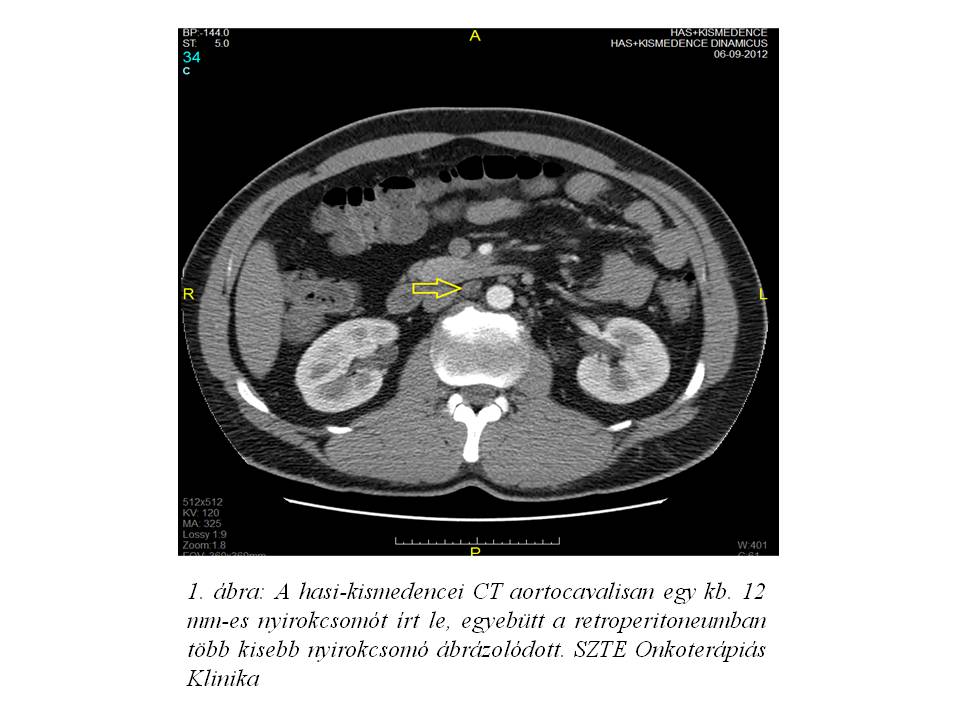

A műtétet követően készült hasi-kismedencei CT aortocavalisan egy kb. 12 mm-es nyirokcsomót írt le, egyebütt a retroperitoneumban több kisebb nyirokcsomó ábrázolódott (1. ábra). Urológiai javaslatra ekkor rutin követés indult, melynek során három havonta váltva UH, illetve hasi-kismedencei CT vizsgálat és tumormarker kontroll történt.